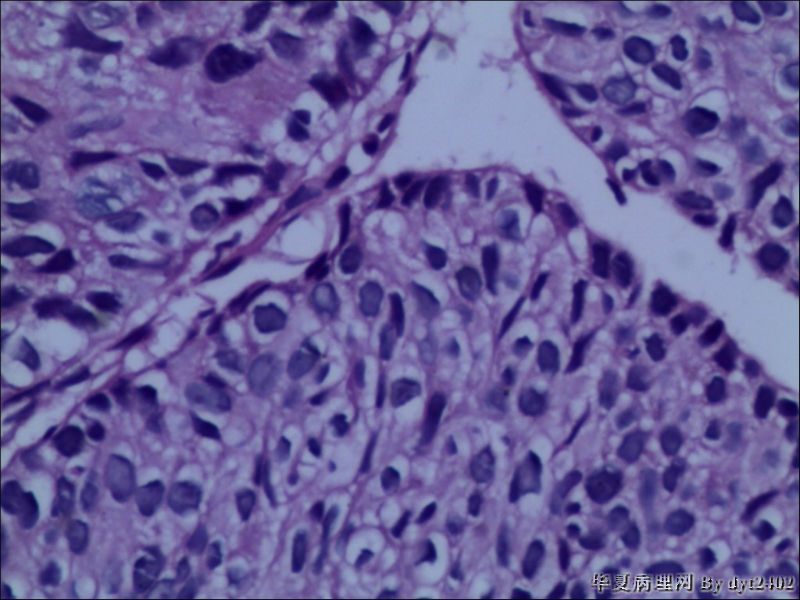

• 宫颈活检 其中一点较迷糊图4

图4

四点中三点是CIN iii,另一点怀疑有更重病变

这个病人是44岁,去年11月底阴道脱落细胞、TCT均见细胞异常,建议活检,病人犹豫,接着单位组织到外院体检时做阴道镜正常,后霉菌感染,此时宫颈未涂醋肉眼看还光滑,直至今年3月来做活检,事前做白带检查又见异常细胞,宫颈未涂醋见后上唇白上皮,涂醋酸后上下唇都有厚白上皮,镶嵌,夹活时上皮剥脱,未能夹到间质,阴道镜医生说至少有CIN III 到原位癌了。。镜下其中3点CIN III无疑,唯有9点处如6、7、11、14等所示结构,但我未见间质浸润,不能说是浸润癌,不知道有没基底细胞样鳞癌的可能,我发了个原位癌不除外深部有更重病变,。